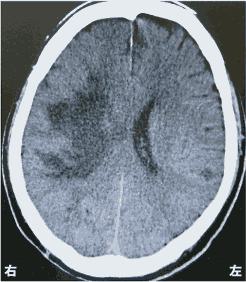

脳梗塞の発生部位によって出現する症状は異なります。この問題では、それぞれの部位における症状を正確に理解することが求められています。

右内包後脚では、左上下肢の運動麻痺が見られるため、この選択肢は正しいです。